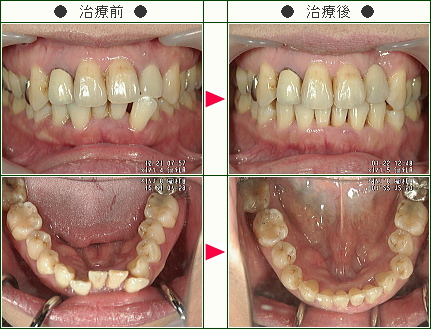

☆デコボコ症例(Yuriyuri様 47歳 女性)

▼患者様の感想

治療期間が短くて済んだ事は良かったです。

何より担当の先生が分かりやすく説明をして下さり、不安要素を取り除いて下さったことで期間を通して安心して治療を受ける事が出来ました。

仕上がりも美しく治療を受けて良かったです。

ありがとうございました。

今後ともよろしくお願い致します。